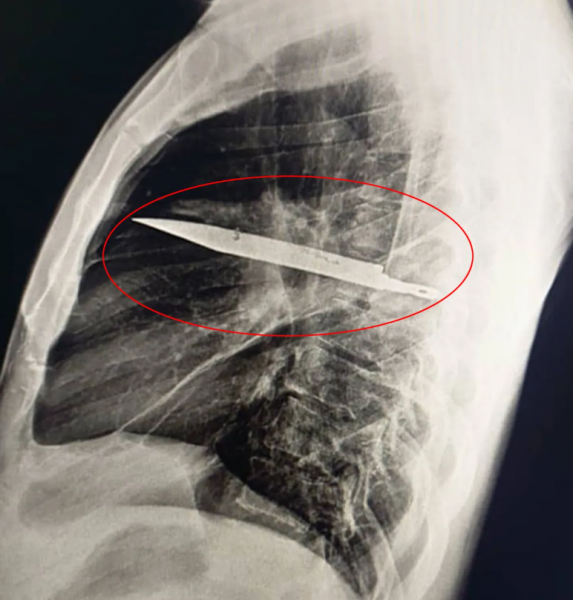

Doctors at the Muhimbili National Hospital in Tanzania recently published a most unusual case study in the scientific journal National Library of Medicine. They wrote about a 44-year-old generally healthy man who came to the hospital with a 10-day-long history of white pus discharge from his right nipple. He denied any chest pain, difficulty breathing, cough, or fever, but asked if he had anything notable to tell doctors, he recalled a violent altercation eight years prior, during which he had sustained several cuts to his face, back, chest, and abdomen. Doctors had managed to suture the wounds back then, and he had lived a mostly uneventful life ever since, up until his nipple started oozing pus. Unable to determine the cause of the infection, doctors ordered an X-ray exam and were shocked to see a giant knife blade lodged in the man’s chest.

Photo: National Library of Medicine

“Initial imaging with a lateral chest radiograph demonstrated a retained metallic object in the mid-thorax, with surrounding opacification likely representing a resolving or chronic loculated hematoma or post-traumatic fibrosis, a sequela of the patient’s stab wound,” doctors wrote in their case study.

Somehow, the knife blade, which had entered through the right scapula, miraculously managed to dodge any major organs. At the time of the man’s altercation, eight years ago, the hospital he was treated at had no means of conducting a radiological investigation, and because he reported no pain after his wounds healed, no one bothered investigating further. Even more bizarre is that the knife caused the 44-year-old patient no discomfort for so long. The pus was a result of the dead tissue that built up around the foreign object.